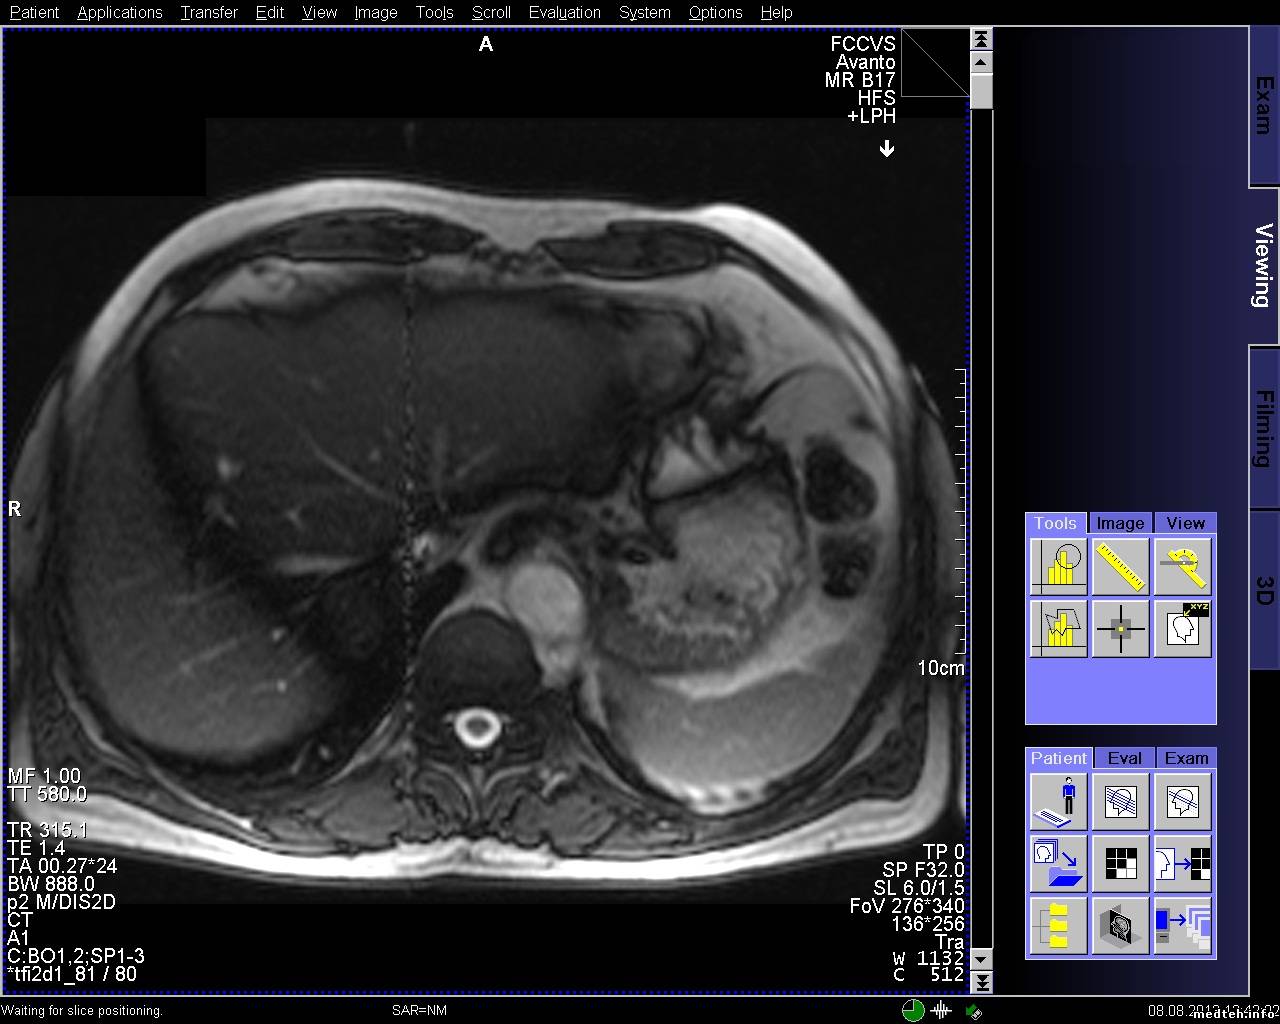

Появились артефакты на изображении при обследованиях сердца. Все тесты качества проходят.

В чём может быть проблема?

8009364.jpg (263.4 Kb) · 5451893.jpg (273.5 Kb) · 9546723.jpg (256.9 Kb)

FedorM, спайк чек проходит, клетка в норме, источников помех нет, в том числе и светодиодных лампочек (был прецедент давненько). Полосы есть на всех направлениях срезов, но отличаются шириной и положением, могут быть узкие или широкие, могут быть сбоку от основного изображения, могут быть по средине.